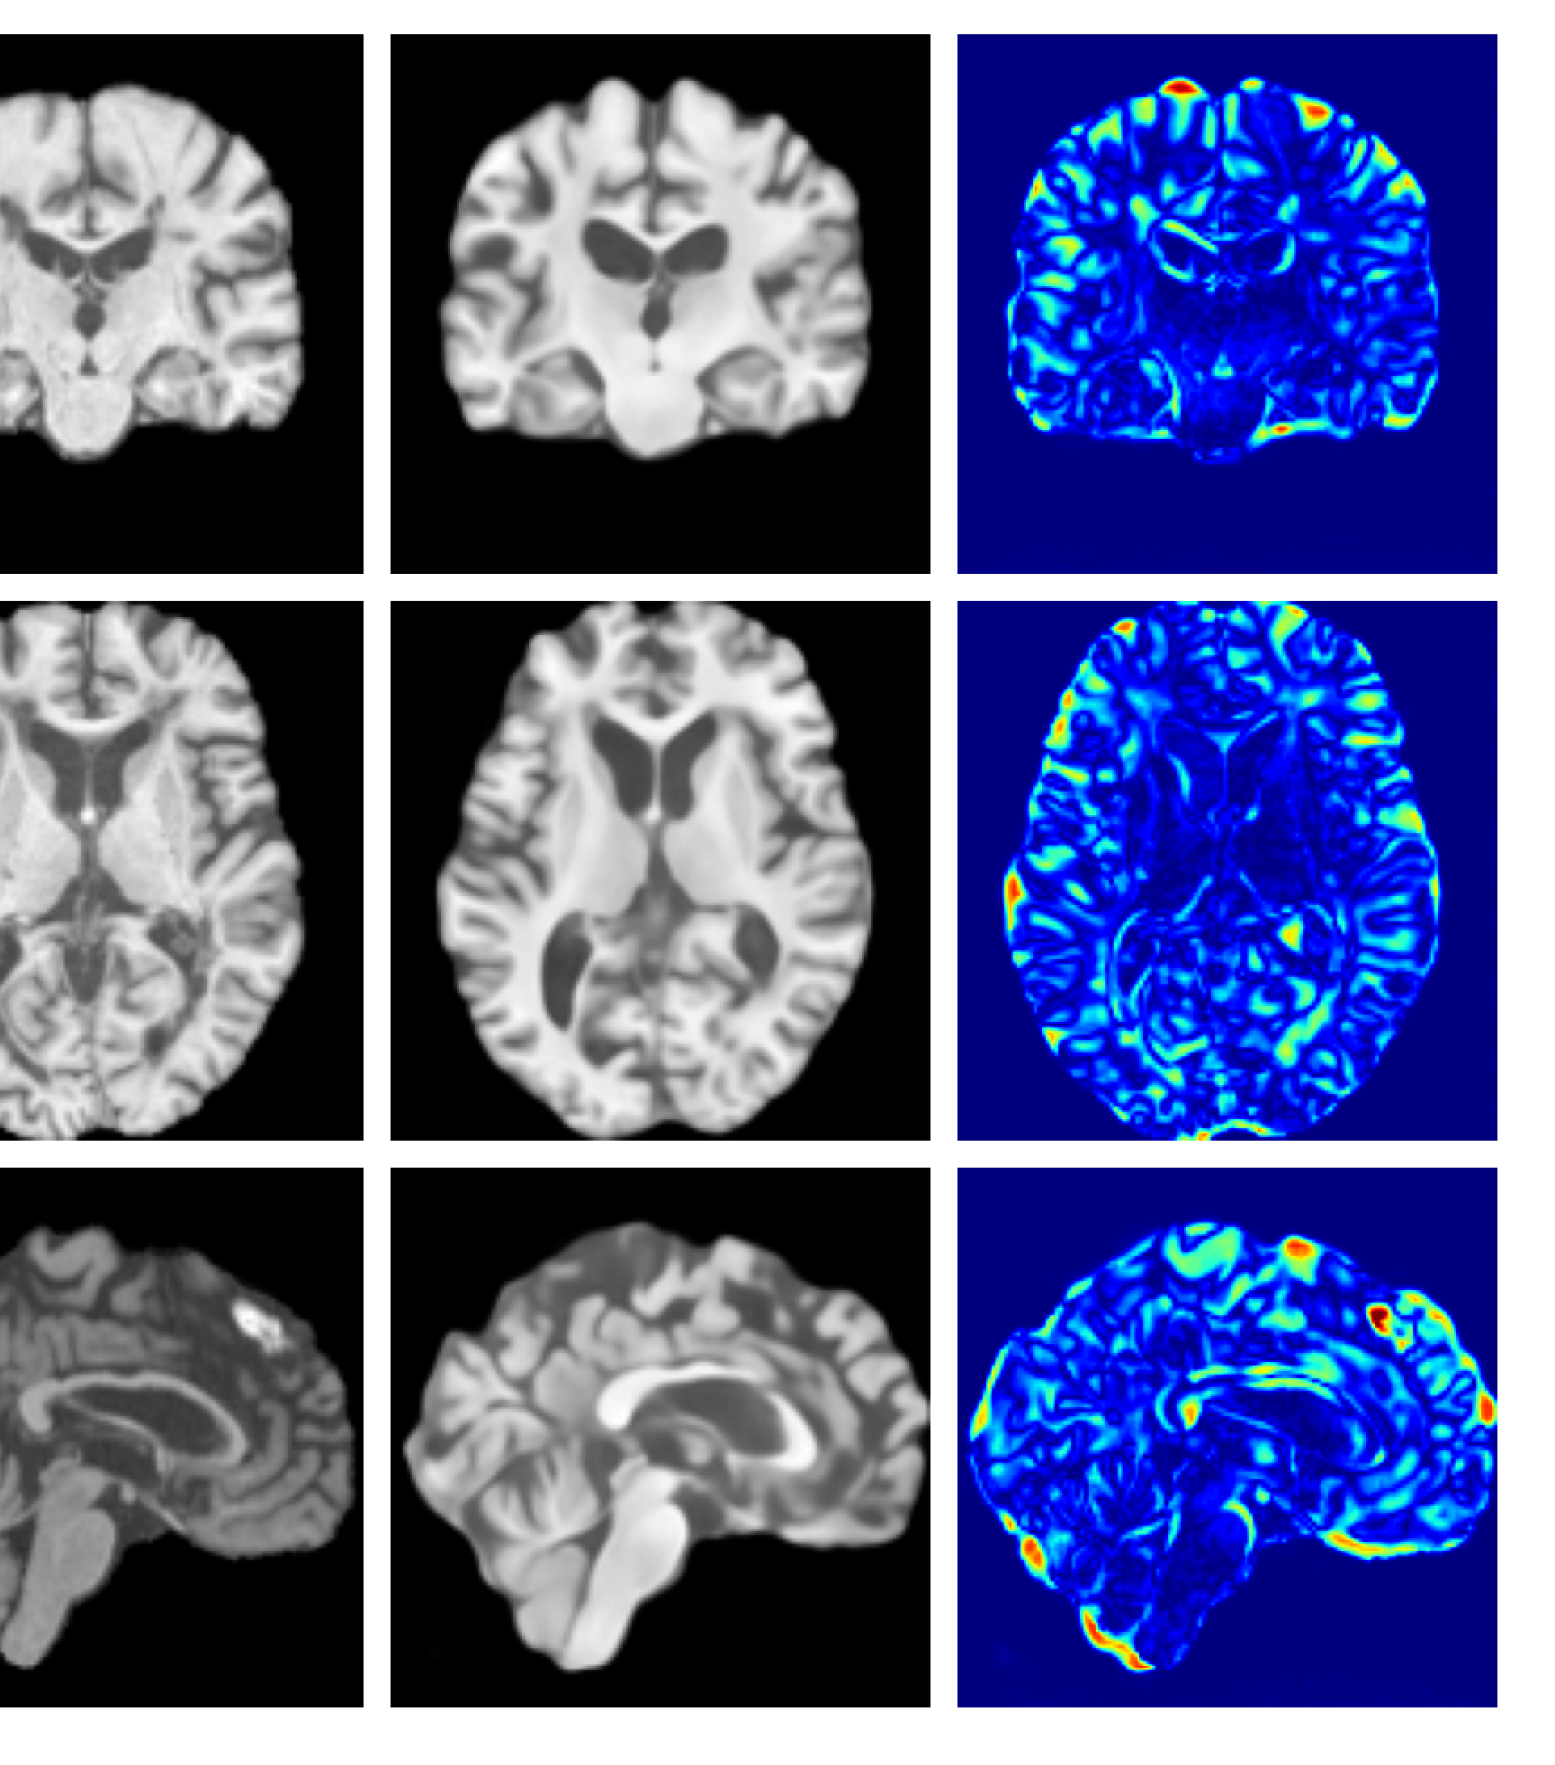

Figure 3: Example reconstructions and anomaly maps for a sample from the disease cohort of the UKBB dataset. Lesion and WMH are indicated in the original image by the red and yellow boxes respectively.

Figures 3 and 4, show example reconstructions and abnormality maps for a sample from the UKBB and UoTH datasets, respectively. Enlarged figures and additional example qualitative results for the ADNI dataset are available in the Supplementary. In Figure 3 we see that whilst all models are able to detect the lesion visible in the sagittal slice, the VAE, cVAE, LDM and LDM (TavgT_{avg}) produce very smooth outputs or lose defining characteristics and thus exhibit more false positives in healthy tissue. THOR and CADD provide the best results, with CADD better detecting white matter hypointensities (WMH). However, neither method fully inpaints all WMH, potentially due to presence of WMH in the healthy training set.

Figures 8 and 9 are enlarged versions of Figures 3 and 4 respectively, with the latter now including results from all compared methods. Figure 10 provides example reconstructions and anomaly maps for an AD subject from the ADNI disease cohort.

Figure 8: Enlarged example reconstructions and anomaly maps for a sample from the disease cohort of the UKBB dataset. Lesion and WMH are indicated in the original image by the red and yellow boxes respectively.